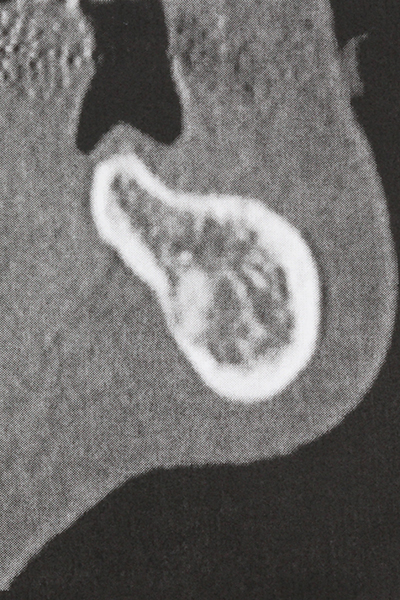

Indication: Sinus lift

Preparation of the lateral window during an external sinus floor elevation is challenging, particularly for implantologists with little surgical experience. Removal of the bone cover of the sinus without injuring the underlying Schneiderian membrane is only part of the operation – after establishing an adequate access, the membranous lining of the sinus must be carefully mobilized to make space for the augmentation materials or the implants. Piezo surgery is useful for this indication in two ways: diamond-coated instruments can be used for selective bone ablation and the underlying mucous membrane remains intact when the procedure is done carefully. The ultrasonic frequencies also enable detachment of the mucous membrane without complications – the frequencies are transmitted into the space between the mucous membrane and sinus floor by special blunt attachments (Cassetta, Ricci et al. 2012, Pereira, Gealh et al. 2014) (Rickert, Vissink et al. 2013). As a result, it is not surprising that current reviews of external sinus floor elevation positively evaluate the use of piezoelectric devices as well as the use of roughened implant surfaces and bone replacement materials (Wallace, Tarnow et al. 2012).